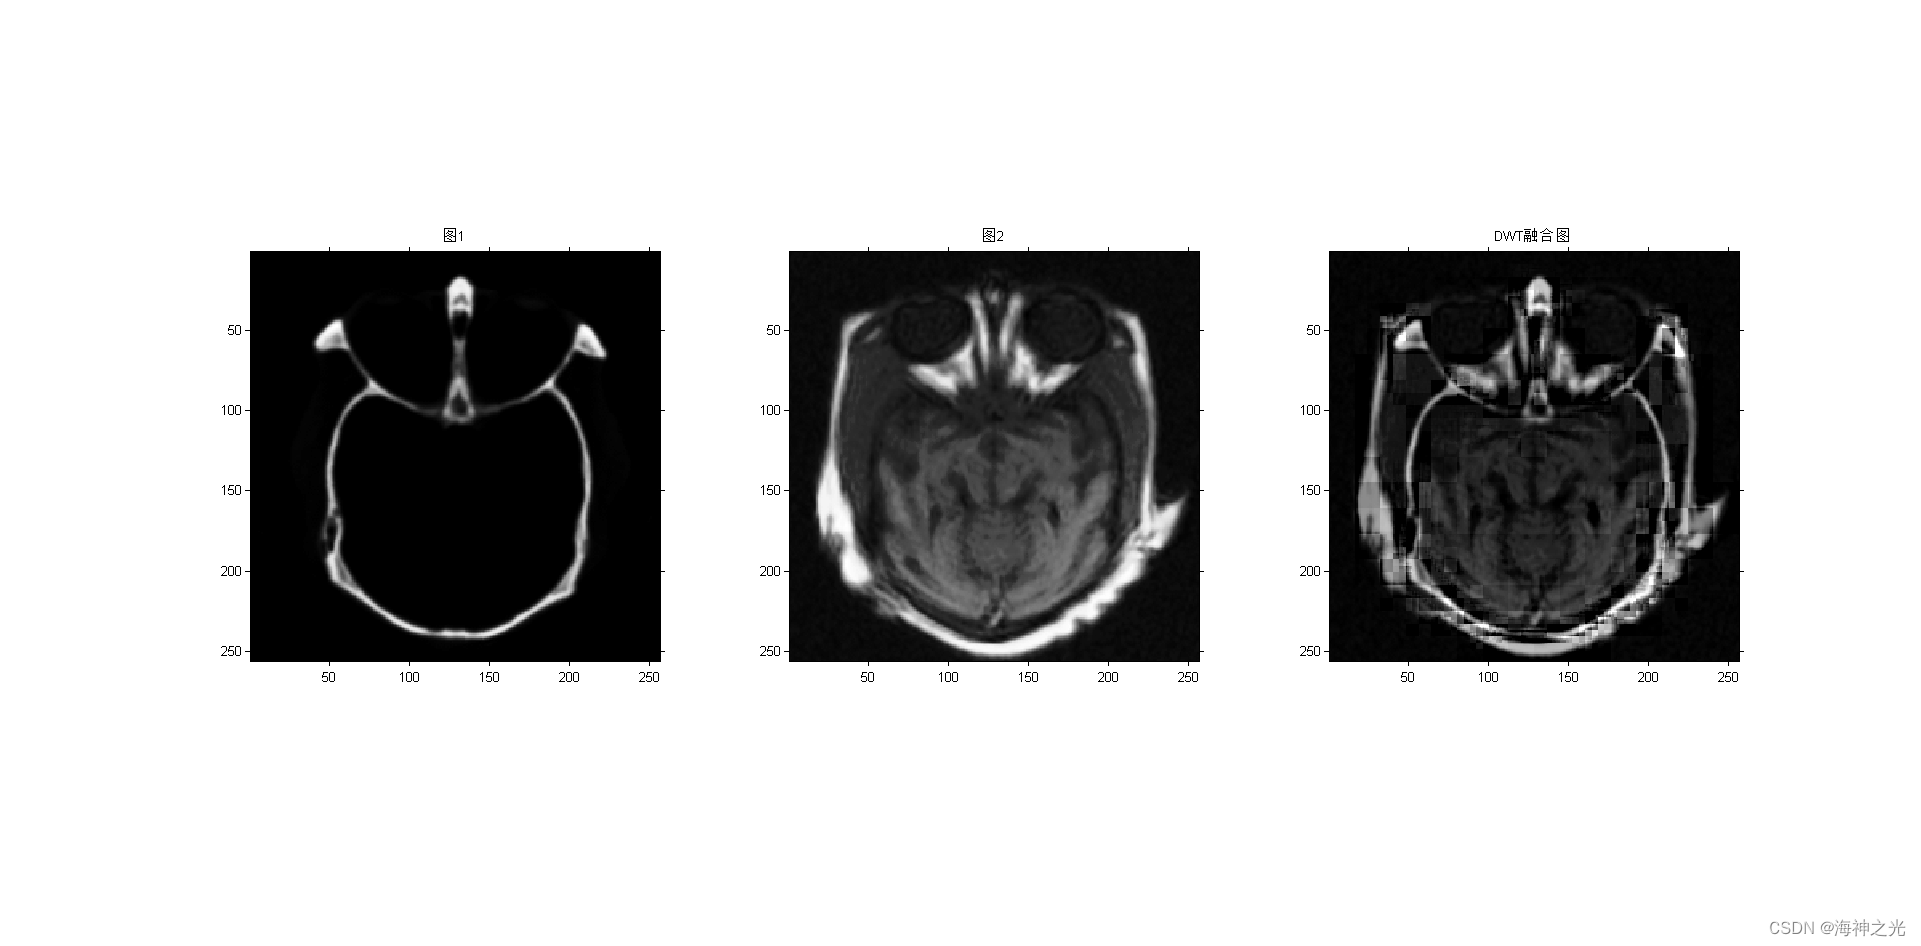

figure;subplot(131);imshow(image_input1);title(‘图1’)

subplot(132);imshow(image_input2);title(‘图2’)

case 3

F = dwt_fuse(A, B, level); %DWT

title(‘DWT融合图’)